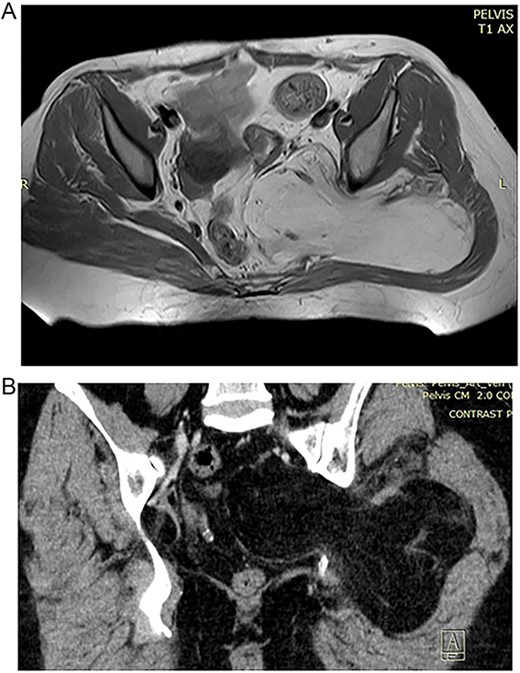

In the 55-year-old female, consequently were done a CT scan and MRI imaging (Fig. 2A and B). The patient had a different surgical history compared to the other female representative. She was operated in another medical unit due to spinal stenosis and nerve root decompression following spinal stabilization was performed. However, the complaints were persistent and on a second MRI, the team of neurosurgeons, who performed the operations on both of the presented cases, noticed a mass corresponding with the characteristics of lipoma and being the predominant reason for the complaints as it caused sciatic pain.

(A) Preoperative CT of the 55 year old patient with lipoma in the pelvic region. (B) Preoperative CT of the 55 year old patient with lipoma in the pelvic region.